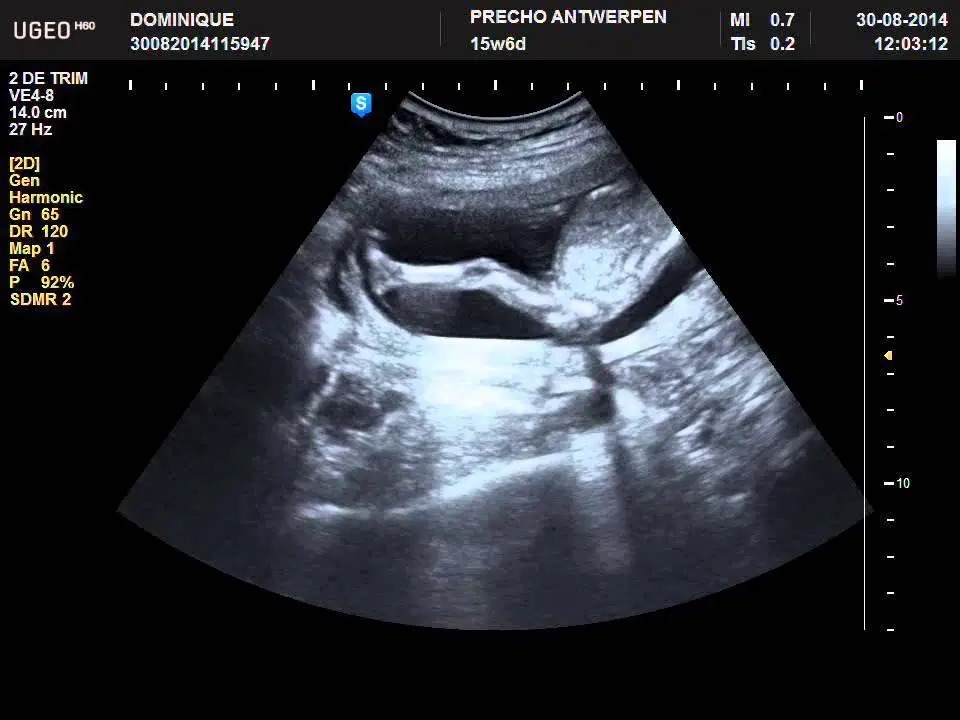

Ngoài ra, khá nhiều người thắc mắc thai 15 tuần biết trai hay gái chưa? Khi thực hiện siêu âm, hình ảnh thai 15 tuần có khả năng cho biết giới tính bởi lúc này cơ quan sinh dục của bé đã được hình thành. Tuy vậy, độ chính xác giới tính ở thời điểm này chưa cao, nhất là khi bé nằm ở tư thế không thuận lợi hoặc bác sĩ chưa có nhiều kinh nghiệm. Mẹ bầu vẫn nên siêu âm thêm ở các tuần sau để biết giới tính của bé chính xác hơn.